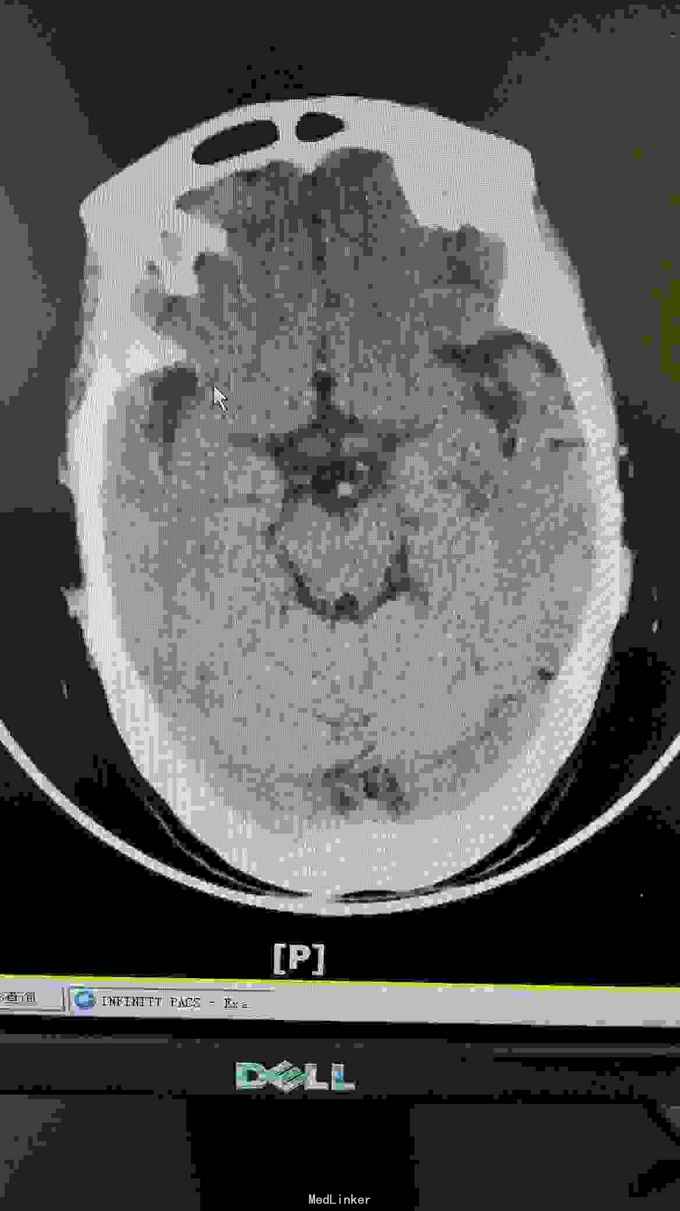

生命体征:耳温:36.8℃ 脉搏:96次/分 呼吸:20次/分 血压:140/67mmHg。pain score: 0/10 发育无异常,口唇无发绀,双肺呼吸音清,未闻及干湿性啰音;心率96次/分,律齐,未闻及明显病理性杂音;腹软,无压痛、反跳痛,肝脾肋下未及,双肾区无叩痛,双下肢无浮肿。神经专科:神清,构音尚清,双侧额纹对称,双眼睑下垂,右侧明显,双侧瞳孔等大等圆,直径约3.0mm,对光++,双眼活动尚可,伸舌居中,鼻唇沟无浅,颈软,四肢肌力5级,双侧肢体肌张力对称,双侧巴氏征未引出,双侧指鼻准,闭目难立征阴性。 血常规三系尚正常。出凝血系列,甲状腺功能 ;存在TSH偏高。肿瘤标志物基本正常范围。糖化血红蛋白正常范围;空腹血糖、血钾正常范围。大小便常规未见明显异常。 胸部CT提示右肺中叶及左肺上叶舌段纤维、增殖灶,请结合临床。颈动脉B超提示左侧颈动脉斑块形成,存在左侧颈动脉硬化。椎动脉B超提示双侧椎动脉未见明显异常。心超提示左室舒张功能下降。腹部B超提示肝、胆、胰、脾未见异常,双肾、输尿管、膀胱未见异常。甲状腺B超提示右侧甲状腺结节。肌电图提示重频试验阴性。心电图提示窦性心律,大致正常心电图。 这个病人因为做过钢板内固定术,所以磁共振没做!可惜了

诊断:双眼睑下垂待查:重症肌无力?动眼神经麻痹待排。2.高血压病?3.心功能不全? 目前治疗上予立普妥20mg调脂稳定斑块,待肌电图检查回报后余新斯的明口服,以及活血化瘀、改善循环等对症支持治疗.

这患者优先考虑重症肌无力,但是以单侧为主,所以动眼神经麻痹也需要排除,因为患者在上级医院做过“新斯的明试验”症状稍改善,持续数小时后又加重,所以等药效过了之后给她做了肌电图,重频试验阴性。1-5波幅下降不明显,结合头颅CT结果,诊断重症肌无力,予新斯的明口服后症状是有改善, 我想请教各位,单单从症状和新斯的明试验可以诊断重症肌无力吗?因为这个病人的肌电图表现是阴性的胸部CT也没看到有胸腺增生。